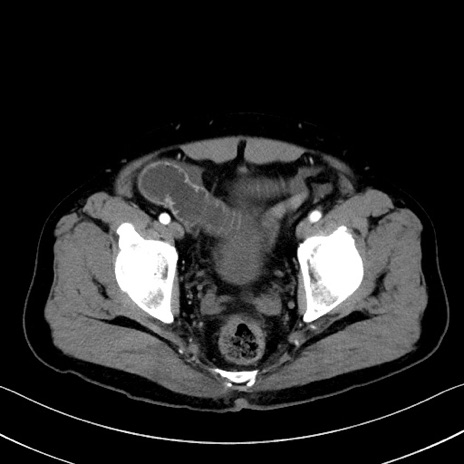

症例35(横断像)

冠状断像

【症例】70歳代 男性

【主訴】腹部膨満、嘔吐

【現病歴】昨日より腹部膨満感出現。本日増悪し、仙痛出現。嘔吐あり、受診。

【既往歴】糖尿病、胆摘後

【身体所見】BP 149/80mmHg、HR 74/min、BT 35.9℃、腹部:膨満、軟、圧痛なし。腸雑音減弱あり。上腹部正中切開瘢痕あり。

【データ】WBC 13500、CRP 1.72